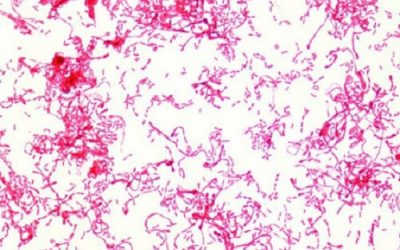

Trực khuẩn gram là tên gọi chung của nhóm vi khuẩn hình que đáp ứng với phương pháp nhuộm gram – một phương pháp phân loại vi khuẩn dựa trên cấu trúc thành tế bào. Trực khuẩn có mặt ở... Xem thêm